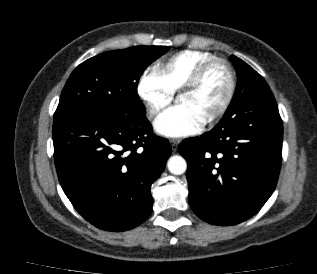

В некоторых случаях, например, при подозрении на опухолевый процесс, проводится КТ легких с контрастированием, когда для лучшей визуализации патологического очага пациенту внутривенно вводится йодсодержащий контрастный препарат. Контрастное вещество накапливается в патологических участках и обеспечивает их яркую визуализацию на фоне неизмененной ткани. С помощью контрастирования можно визуализировать кровеносные сосуды, выявить первичные опухоли и метастазы в легких, дифференцировать новообразования, например, отличить доброкачественную опухоль от злокачественной.

В медицинском центре «Доступная медицина» установлено современное оборудование – 64-срезовый и 128-срезовый компьютерные томографы TOSHIBA AQUILION, на которых проводится сканирование легочной ткани. За счет увеличенного количества детекторов аппараты производят снимки с большой скоростью и минимальной дозой облучения. При этом инновационные цифровые приложения позволяют получить объемные изображения легочной ткани высокой четкости, контрастности и в мельчайших подробностях.

• патологию легочных сосудов (аневризмe, эмболии.);

• патология сосудов, тромбозы;